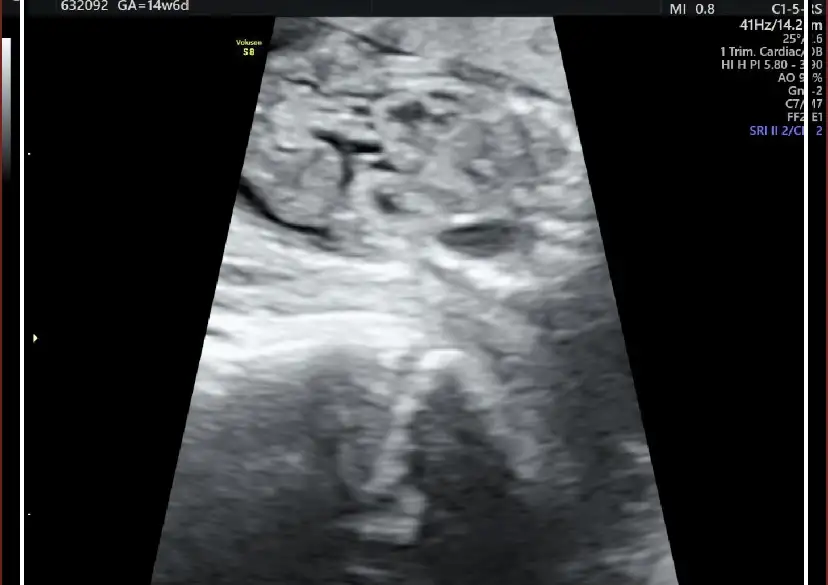

nerden başlasam bilemiyorum o kadar aklım karışıkki ne yapacağımı bilemiyorum lütfen fikirlerinizi yazın. son adet tarifime göre 15 haftalık hamileyim bebeğin kalp atışını duyana kadar günü tutuyordu. sonra 12 haftalıkken kontrole gittim gününden sapmış hastalıklı bir bebek olma ihtimalinin olduğunu söyledi doktor başka doktorada göründüm oda perinatolojiye yönlemdirdi.2 gün önce gittim.15 haftalık gebeliğim,16+5 olarak gözüküyordu. doktor o kadar şey saydıki bebeğin yaşama ihtimali yok dedim ama doktor doğabileceğini ama doğsa bile yaşama ihtimalinin çok düşük olduğunu söyledi.ense kalınlığı ve burun kemiğinin küçük oluşundan down sendromlu olduğunu. iki bacağınında eğri ve kısa olduğunu. iki böbreğininde çalışamaz durumda olduğu için vücudunun su topladığını böbreklerinin iflas ettiğini ve karnında oluşan fıtıktan dolayı karaciğer ve bağırsaklarının dışarda olduğunu söyledi. böylelikle dünyam başıma yıkıldı sonlandırmak gerektiğini ve bunun günah olmadığını söyledi doktor. öyle bir durumdaydımki sonlandırmak bile benim için umuttu ama diyanet danışma hattını aradım bana bebek karnımda olduğu sürece bana zarar verme riski bulunmadıkça günah olduğunu söyledi. bebeğin kalbinde bir sıkıntı yok yaşar diye korkar mı bir anne kendimi çok kötü hissediyorum ölmesini istediğim için. ama doktor yaşarsada zihinende bedenende ileri derece özürlü olacağını tuvalete bile gidemeyeceğini söyledi hem onun için hem bizim için çok zor bir süreç olduğunu yaşlarımızında daha çok genç olduğunu sonlandırmak gerektiğini söyledi.sonlandırırsam ilerde daha kötüsü gelir başıma diye korkuyorum zaten bugüne kadar ne konuşursam başıma bela olarak tekrar karşıma çıkıyor elim kolum bağlı bir durumda amniyosentez testimin sonucunu bekliyorum.aşağı bebeğin bir kaç görüntüsünü bırakacam ben pek bir şey anlamasamda belki siz anlarsınız.